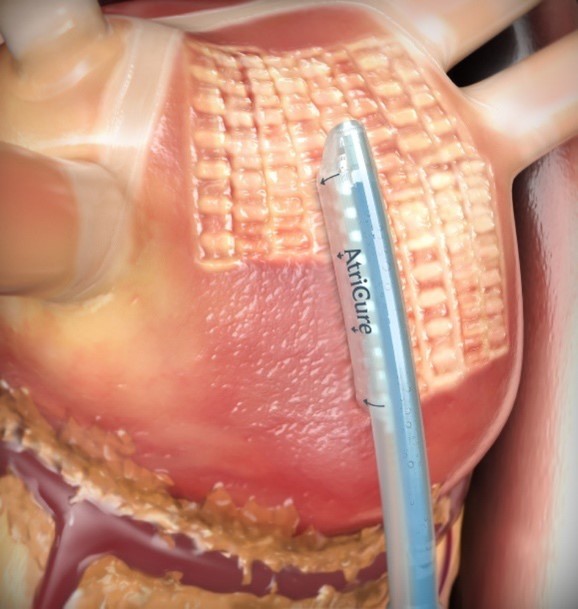

There are several manuscripts which outline the step-by-step procedural steps of the 1st stage epicardial Convergent procedure in detail [14, 15]. In this portion of the manuscript, we will focus more on discussion points and less on the step-by-step operative approach. A TEE is performed to rule out the presence of left atrial or appendage thrombus. A temperature probe is placed into the esophagus as position behind the left atrium. A subxiphoid incision is made and the pericardium is entered in the standard fashion, as close to the diaphragmatic surface as possible. The presence of significant adhesions is excluded. Under direct endoscopic visualization the Convergent cannula is placed into the pericardial space, and landmarks are identified: the coronary sinus and the right and left inferior pulmonary veins. The unipolar radiofrequency ablation catheter is then advanced via the cannula and onto the epicardial surface of the posterior left atrium and ablation is performed, monitoring esophageal temperature and feedback from the device regarding the quality of the ablation (Fig. 2). Upon completion of all accessible territories of the posterior left atrial wall, a drain is placed, and the device and cannula are removed. The incision is closed in the standard fashion.

Fig. 2.

Fig. 2.Epicardial Convergent Procedure Ablation (permission received from AtriCure™).